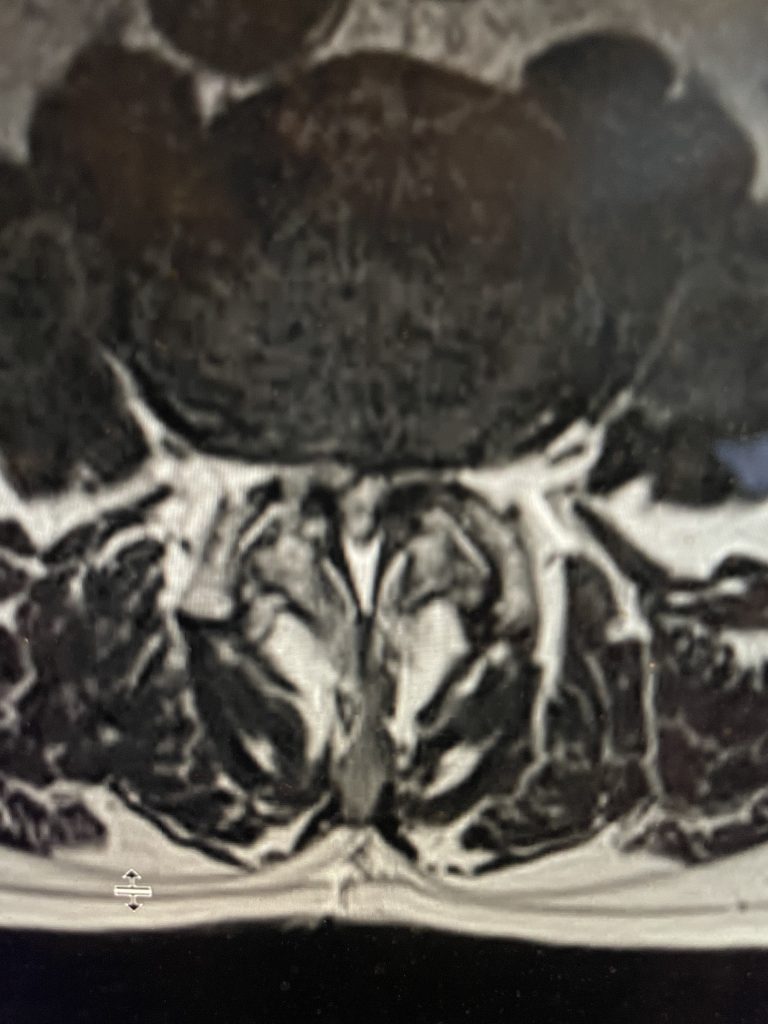

Figure 3. Lateral and AP lumbar intraoperative fluoroscopic images after pedicle screw placement for L3-4 fusion

we augmented our decompression with an instrumented fusion at that level, particularly because of the degree of facet joint removal to adequately decompress him (Fig 3). The facet joints were very overgrown and because of that just undercutting the facet would not prove adequate. These facet joints are enlarged because the patient had degeneration of the cartilage and ligaments of the joints, disc space and supporting structures. A common occurrence is for the spinal segment to slip or “listhes” in Greek. In order to compensate for this instability, the body tries to compensate and enlarges what it has available like the joints and the ligaments. In doing so the spine paradoxically hurts itself in creating spinal stenosis. The bone really does not communicate with the nerve sac and therefore the sac is squeezed because of these enlarged structures. The patient did well postoperatively with relief of his left leg pain and ambulated the same day of his surgery.